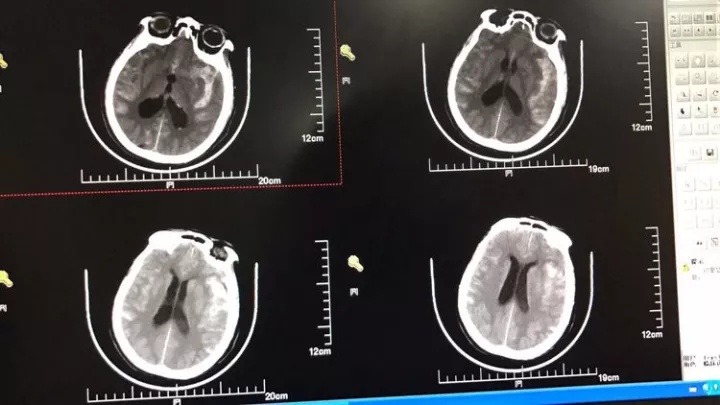

男,49岁,蛛网膜下腔出血

左侧后交通动脉瘤,胚胎型大脑后动脉

3D

局部观,宽颈,涉及颈内动脉和后交通动脉

椎动脉造影见左侧大脑后动脉P1段很细